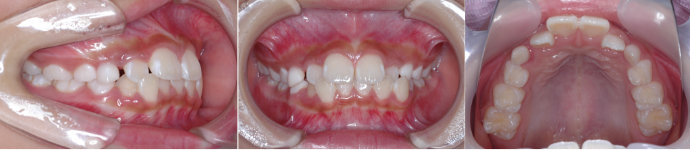

| Case2 |

| 出っ歯 |

| <治療前> |

| <治療後> |

| 主訴 |

上の前歯が出ている |

| 診断名 |

上顎前突 |

| 年齢 |

8歳 |

| 使用装置 |

マルチブラケット装置/ヘッドギア |

| 抜歯部位 |

永久歯の抜歯は無し |

| 治療期間 |

3年6か月 |

| 治療費概算 |

検査・診断料:5万円+税 装置・技術料:25万円+税 来院ごとの処置・管理料:5,000円+税 保定装置料:5万円+税 |

| リスク・副作用 |

特になし |